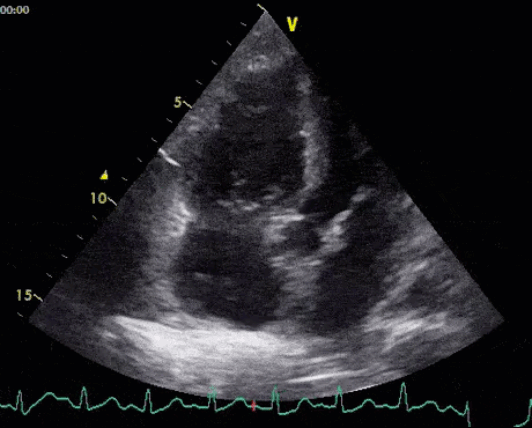

The LV is a good place to start, especially in the setting of myocarditis and cardiomyopathy. Case reports have described LV systolic dysfunction,6 takotsubo cardiomyopathy,7 and wall motion abnormalities.8

Eyeball assessment of LV systolic function is adequate, as the priority is to identify a major problem. This should be assessed by examining 3 aspects of LV function: endocardial excursion, myocardial thickening, and movement of the mitral valve.

- Endocardial excursion: This is the movement of the walls of the LV into the chamber. The endocardium should move symmetrically toward the center of the LV during systole.

- Myocardial thickening: This refers to the increase in the thickness of the myocardium by about 40% in all LV segments during systole. This should occur symmetrically.

- Mitral valve movement: In a heart with normal LV systolic function, the anterior leaflet of the mitral valve should come within 1 cm of the septum in early diastole.

New global LV systolic dysfunction is suggestive of myocarditis, while regional wall motion abnormalities are more suggestive of ACS.